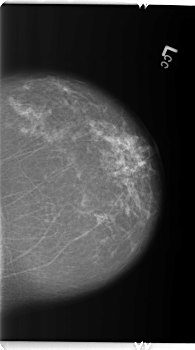

ics_version 1.0 filename B-3362-1 DATE_OF_STUDY 14 8 1997 PATIENT_AGE 77 FILM FILM_TYPE REGULAR DENSITY 2 DATE_DIGITIZED 4 6 1998 DIGITIZER LUMISYS LASER SEQUENCE LEFT_CC LINES 5936 PIXELS_PER_LINE 3304 BITS_PER_PIXEL 12 RESOLUTION 50 NON_OVERLAY LEFT_MLO LINES 5888 PIXELS_PER_LINE 3528 BITS_PER_PIXEL 12 RESOLUTION 50 NON_OVERLAY RIGHT_CC LINES 5896 PIXELS_PER_LINE 3040 BITS_PER_PIXEL 12 RESOLUTION 50 OVERLAY RIGHT_MLO LINES 5896 PIXELS_PER_LINE 3312 BITS_PER_PIXEL 12 RESOLUTION 50 OVERLAY |